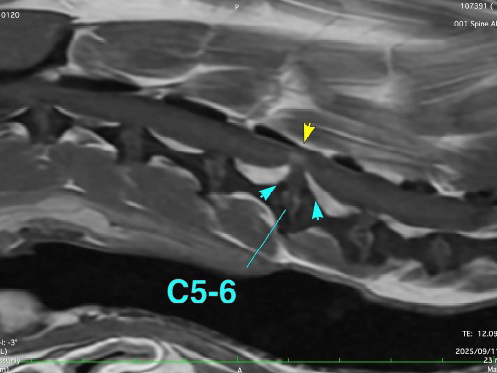

ある日、ワンちゃんが突然立てなくなった(起立困難)とのことで、当院に来院されました。 神経学的な検査を行ったところ、四肢すべてに麻痺が生じている疑いがあり、脊髄の障害が強く疑われました。 詳しく調べるために、麻酔下でMRI検査を実施した結果、第5?6頸椎に重度の椎間板ヘルニアが確認され、これが症状の原因(責任病変)と診断されました。 症状の発症から10日目に、神経の圧迫を取り除く手術(ベントラルスロット術)を実施しました。 手術の翌日には、自分で立ち上がることができるようになり、ふらつきながらも歩行が可能となったため、無事に退院となりました。

MRI検査による責任病変の評価